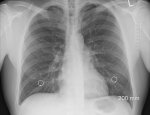

Врач-онколог назвал симптомы рака легких:

- Кашель, который не проходит в течение трех недель

- Инфекции грудной клетки, которые продолжают возвращаться

- Кровохарканье

- Боль или боль при дыхании или кашле

- Постоянная одышка

- Постоянная усталость или недостаток энергии и/или

- Потеря аппетита или необъяснимая потеря веса

Поскольку это третий по распространенности вид рака, крайне важно, чтобы любой, кто испытывает какие-либо из этих симптомов, обратился к врачу.